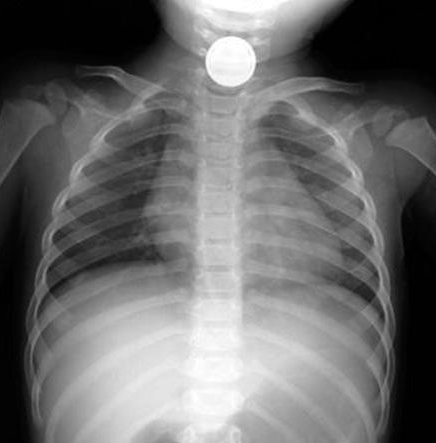

兒童及嬰幼兒服裝上的拉鏈頭、鈕扣等附件,大都屬于小零件。如果拉鏈頭、鈕扣等服裝上的附件固定不牢固而松脫,可能會造成兒童誤吞或吸入,這些附件進入呼吸道后可能會堵塞呼吸道導致窒息;進入消化道后,會導致腸梗阻、腸管擴張,嚴重時會導致腸穿孔、腸壞死,甚至存在生命危險。國內(nèi)已發(fā)生多起由類似小零件導致的傷害事故,示例如下:

圖2 兒童誤吞小零件導致窒息